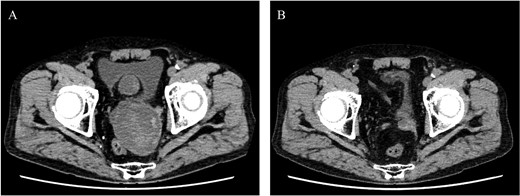

An 80-year-old female was admitted for the expansion of a left CIAA and IIAA. Ten years prior, she had undergone coiling of peripheral branches of the IIAA and stent graft placement in the CIAA. Contrast-enhanced CT showed the IIAA and CIAA extending into the deep pelvis. The maximum short diameter was 90 mm, and there were no signs of endoleak (Fig. 4).

Preoperative computed tomography imaging showing a left common iliac artery aneurysm and internal iliac artery aneurysm with a maximum short diameter of 90 mm. A—Axial image, B—3D image. LCIAA, left common iliac artery aneurysm.

Postoperative computed tomography showing a reduction in aneurysm size. A—Preoperative image, B—7-month postoperative image.